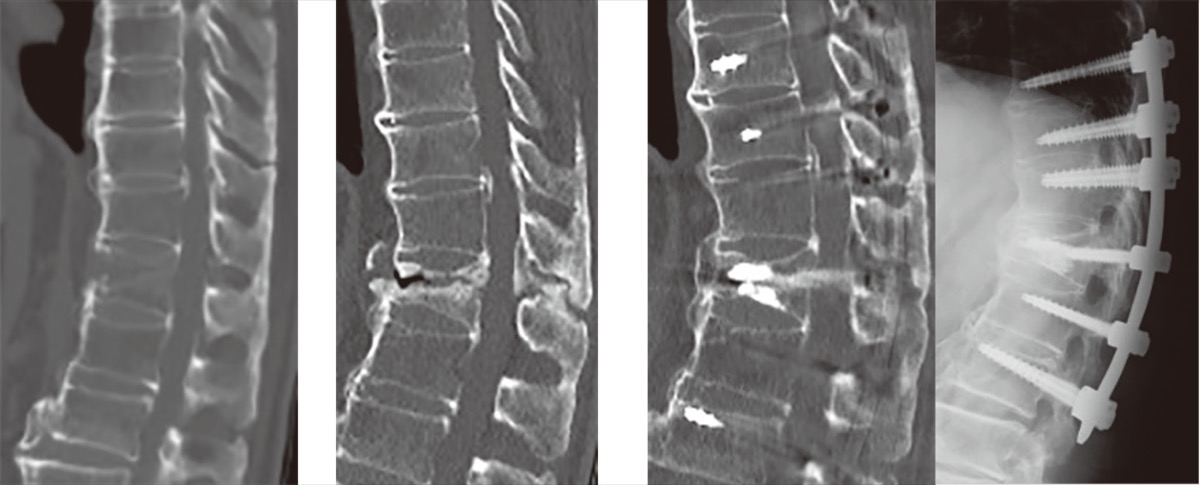

前回、脊椎靭帯骨化症についてお話ししましたが、これに関連した疾患にびまん性特発性骨増殖症(diffuse idiopathic skeletal hyperostosis:DISH)があります。脊椎では前縦靭帯を中心に広範囲で骨化を生じ、胸椎に多く認めます。日本人の有病率は約10%との報告があり、70代以上の高齢男性では約40%との報告もあります。

骨化が腰椎にまで及ぶと脊椎の可動性が低くなり、腰の曲げ伸ばしが困難になります。また、骨化せず可動性が残った脊椎に負荷がかかるため、その部位が変形して痛みや神経障害を生じたり、骨折を発症することもあります。DISHに関連した骨折は近年増加傾向にありますが、通常と比べ骨折部への負荷が大きくなり自然治癒しづらいため、手術が必要になる可能性が高いです。